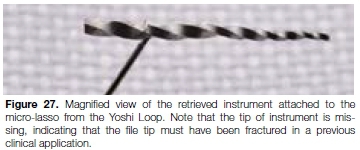

Under magnification, the preformed loop was carefully placed around the exposed coronal aspect of the file. The loop was tightened around the fractured file by moving the retraction button on the loop system. The loop device was then used to slowly pull the loosened fragment from the root canal system (Figure 26). Figure 27 shows a magnified view of the retrieved instrument attached to the micro-lasso from the Yoshi Loop. Note that the tip of instrument is missing, indicating that the file tip must have been fractured in a previous clinical application prior to the case presented in this case report.